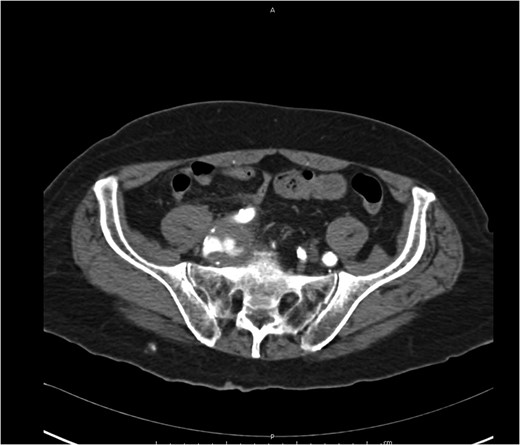

At Emergency department, physical exam showed hypotension blood pressure 70/50 mmHg and per rectal exam showed blood clot with enlarged prostate. After resuscitation until stable vital sign, he was sent for colonoscopy but cannot be evaluated due to a lot of blood clots in the rectum. He was admitted for observation and we planned to repeat colonoscopy again following day because he was stable and bleeding was stopped. Following day after admitting, he had massive lower gastrointestinal bleeding again fresh blood ~1000 ml from his anus. His blood pressure was lower 80/50 mmHg. After stabilization, we planned to send the patient to angiogram for embolization. But the patient had a problem vascular access site and then send to computed tomography angiography (CTA) for evaluate access site. We found 3 cm aneurysm of right internal iliac artery with partial thrombus and attached to rectosigmoid colon with leakage of contrast into sigmoid lumen (Figs 1–2). He was sent to operating room during transferring we gave blood transfusion and then emergency explore laparotomy was performed, the operation performed by partial aneurysmectomy, ligated right internal iliac, wedge resection rectum wall and temporary abdominal closure with swab packing due to bowel distension and abdominal pressure was high. The operative time was around 3 hours and blood loss 6000 cc. He was sent to operating room for change swab packing on Day 3 and permanent abdominal closure on Day 5. During postoperative period, he developed acute cholecystitis and underwent open cholecystectomy. After admit for 1 month, he was discharged with fully recovery.

Axial view iliac aneurysm with partially thrombose contact rectosigmoid colon and contrast leak.